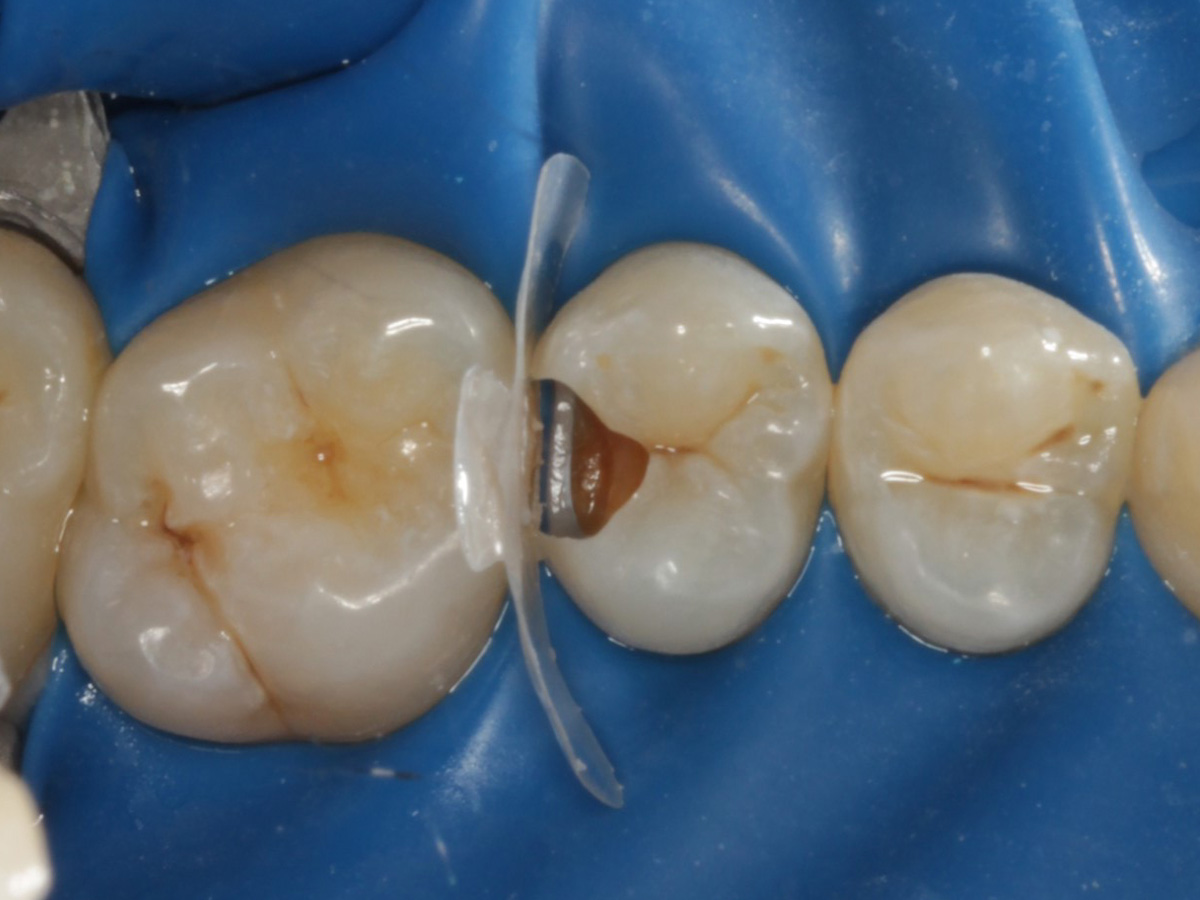

Abbildung 5

Defektdarstellung